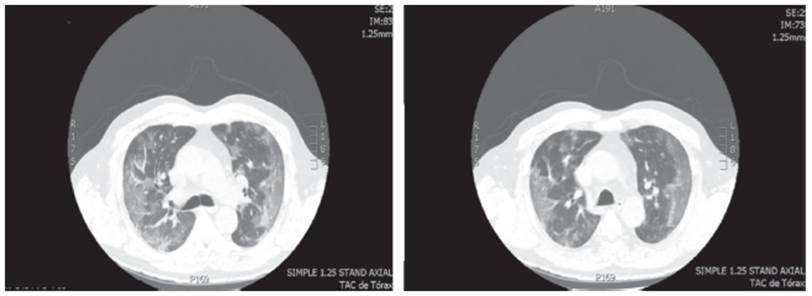

El examen físico de ingreso mostró una tensión arterial (TA) de 130/60 mmHg, frecuencia cardiaca (FC) de 108 latidos por minuto, frecuencia respiratoria (FR) de 18 respiraciones por minuto, saturación de oxígeno de 91%, tirajes universales, crépitos en ambas bases pulmonares, cianosis distal y llenado capilar superior a 4 segundos. Se realizó una radiografía de tórax que mostró infiltrados intersticiales bilaterales universales y una tomografía axial computarizada (TAC) de tórax (Figura 1) que evidenció imagen en vidrio esmerilado universal, zonas de crazy paving y broncograma aéreo en base pulmonar derecha. En la Tabla 1 se reportan los paraclínicos realizados al ingreso y durante estancia en la unidad de cuidados intensivos (UCI).

Fuente: Documento obtenido durante la realización del estudio.

Figura 1 Tomografía axial computarizada de tórax, caso 1.